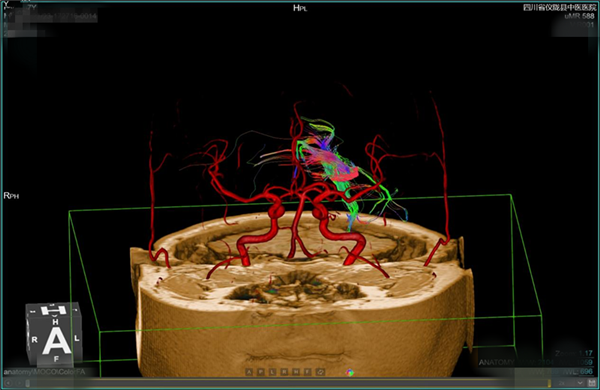

(五)血管成像:无需注射对比剂,对全身血管进行扫描,先进的多角度后处理重建,保证了扫描区域内血管的连续性。用于检查颅内、颈部以及四肢的动脉瘤、动静脉畸形、静脉病变等。

头颅血管与神经联合显示

血管成像图